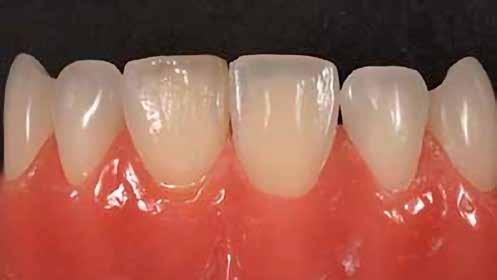

14. ábra: Egy moláris fog preoperatív állapota.

15. ábra: Egy moláris fog postoperatív fotója.